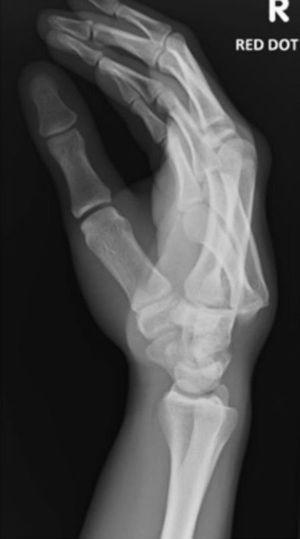

3rd and 4 th carpometacarpel joint dislocation

Lateral x-ray of the right hand. Dislocation of the 2nd and 3rd metacarpal? Closed fracture? Soft tissue in the X-ray shows some swelling to the dorsum part of the RT hand

Marker on the far upper right indicates it’s the RT hand. I agree with the metacarpal

X ray of left hand shows third and fourth metacarpel dislocation.....